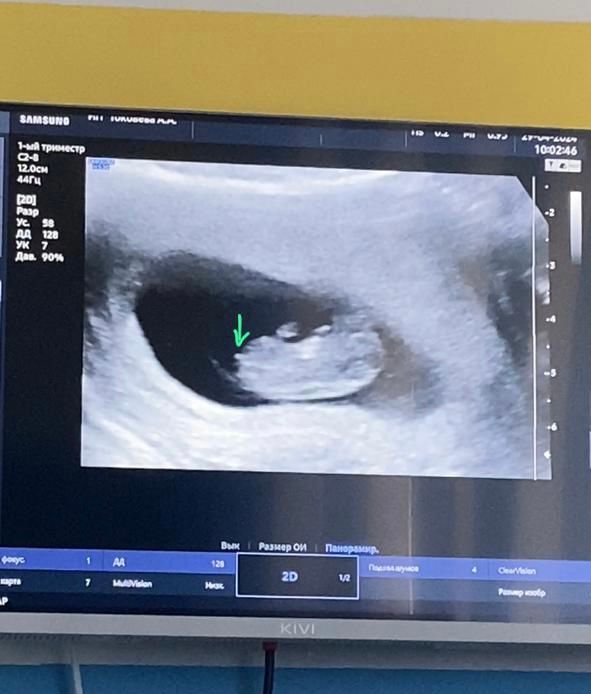

Узи 9-10 недель.

Ольга, Вот когда мне показывали снизу там что-то прям торчало,но возможно и пуповина так себя показала)

Я вообще пока сардельку вижу 😂мне кажется раньше 12 недель не стоит смотреть точно))) даже на бугорок

в 13 девочку самый крутой узист города поставил, а в 18 уже мальчиком стал. там не видно еще ничего, тем более того, что вы указываете на фото))))подождите еще чуть чуть